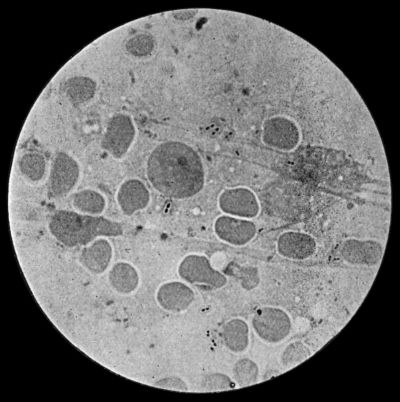

| 3. | Streptococci in Pus from case of Diffuse Cellulitis | 26 |

Cocci or micrococci are minute round bodies, averaging about 1 µ in diameter. The great majority are non-motile. They multiply by fission; and when they divide in such a way that the resulting cells remain in pairs, are called diplococci, of which the bacteria of gonorrhœa and pneumonia are examples (Fig. 5). When they divide irregularly, and form grape-like bunches, they are known as staphylococci, and to this variety the commonest pyogenic or pus-forming organisms belong (Fig. 2). When division takes place only in one axis, so that long chains are formed, the term streptococcus is applied (Fig. 3). Streptococci are met with in erysipelas and various other inflammatory and suppurative processes of a spreading character.

Fig. 3.—Streptococci in Pus from an acute abscess in subcutaneous tissue. × 1000 diam. Gram's stain.

Streptococcus Pyogenes.—This organism also varies greatly in its virulence; in some instances—for example in erysipelas—it causes a sharp attack of acute spreading inflammation, which soon subsides without showing any tendency to end in suppuration; under other conditions it gives rise to a generalised infection which rapidly proves fatal. The streptococcus has less capacity of liquefying the tissues than the staphylococcus, so that pus formation takes place more slowly. At the same time its products are very potent in destroying the tissues in their vicinity, and so interfering with the exudation of leucocytes which would otherwise exercise their protective influence. Streptococci invade the lymph spaces, and are associated with acute spreading conditions such as phlegmonous or erysipelatous inflammations and suppurations, lymphangitis and suppuration in lymph glands, and inflammation of serous and synovial membranes, also with a form of pneumonia which is prone to follow on severe operations in the mouth and throat. Streptococci are also concerned in the production of spreading gangrene and pyæmia.

Division takes place in one axis, so that chains of varying length are formed (Fig. 3). It is less easily cultivated by artificial media than the staphylococcus; it forms a whitish growth.